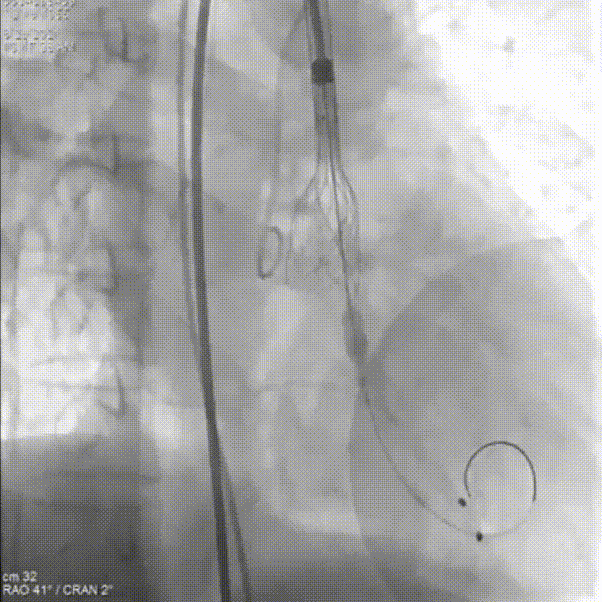

主动脉根部造影

第一次尝试释放

位置偏深回收调整,进行第二次释放

瓣膜流入端被压缩有上跳风险,再一次进行回收

第三次释放